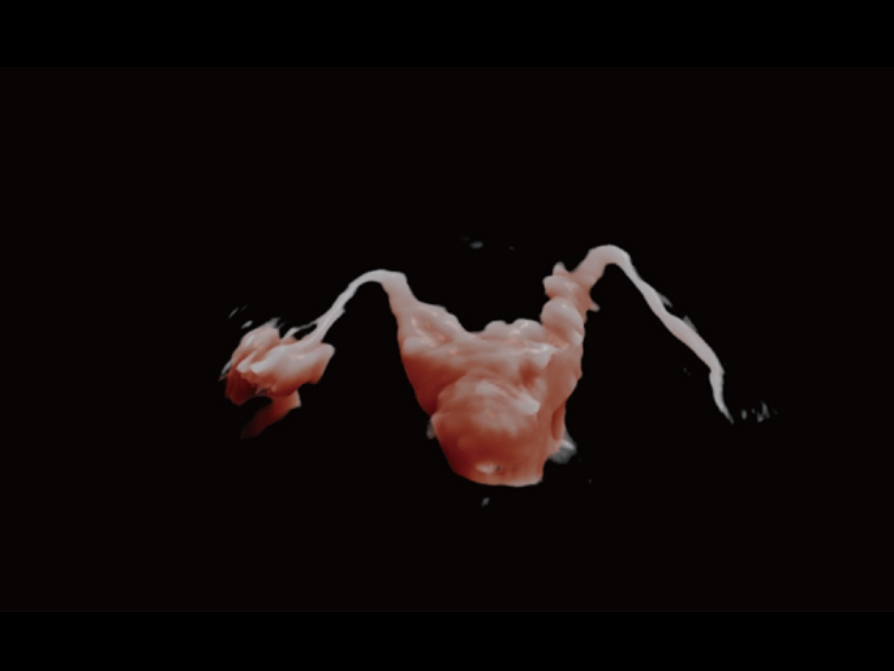

Comprehensive upgrading on iLive to significantly improve the detailed resolution as well as anatomical realism. Hyaline is a new rendering method that dynamically applies transparency to rendered structures for a more comprehensive view of anatomy, therefore better displaying internal anatomy from a solid surface.